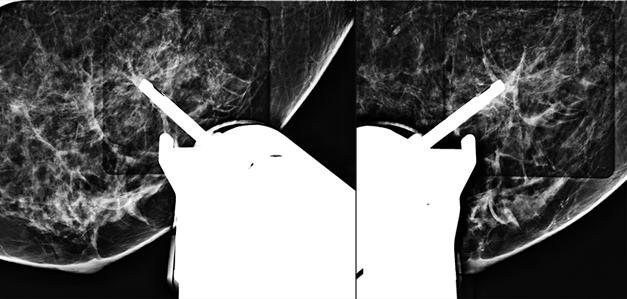

Quickly reach challenging lesion locations.

A fully integrated C-arm and bidirectional patient positioning provide a new level of 360° access to the breast, improving access to some of the most challenging lesions.1 The system features an independently rotating biopsy arm and exclusive lateral needle approach that allows clinicians to switch from a standard to lateral approach in seconds—without additional attachments and without the need to reposition the patient or acquire additional images.